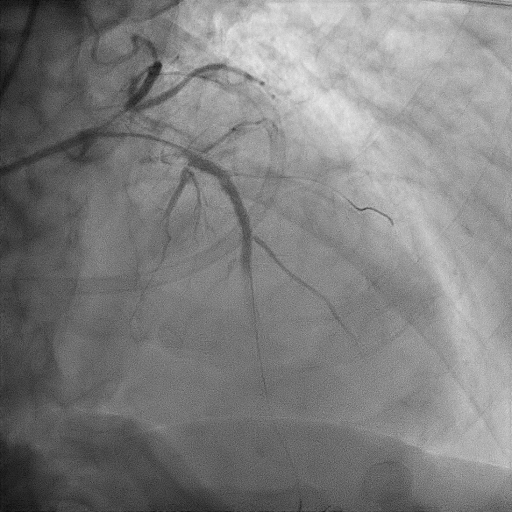

We proceeded with delayed selective PCI to the left anterior descending artery (LAD). The left main coronary artery (LMCA) was engaged with guiding catheter Medtronic Launcher 6FR EBU 3.5. The PTCA guide wire Shun R (SHUNMEI Medical) crossed the lesion with ease. Besides, we wired the diagonal 1 with PT2 (Boston Scientific) to provide side branch protection. The proximal to mid segment of the LAD lesion was pre-dilated with Sapphire NC 24 PTCA balloon 3.0x15mm and inflated to 12 atm. The lesion was stented with Xience Xpedition 3.0x48mm and inflated to 10atm. The stent was post-dilated with NC Trek balloon 3.5x12mm and inflated to 14atm. Noted while retracting the balloon during post-dilatation, the guiding catheter advanced deep into the LMCA several times. Subsequently, patient became progressively hemodynamically unstable. Trial of aspiration with Genoss Extractor but no thrombus was aspirated. Intracoronary Tirofiban bolus was administered. Unfortunately, patient went into cardiorespiratory arrest and intensive resuscitation was commenced. Angiography showed severe flow-limiting type D dissection of the LMCA. We proceeded with rescue stenting of LMCA with Xience Sierra 3.5x38mm with inflation to 12atm. The stent was post-dilated with NC Euphora 4.0x8mm and inflated to 18atm. The final result was TIMI flow 3 but the stent was about 3 to 5 mm proximal to the LMCA ostium. An intra-aortic balloon pump was also inserted and patient required 4 inotropes.

Case Summary